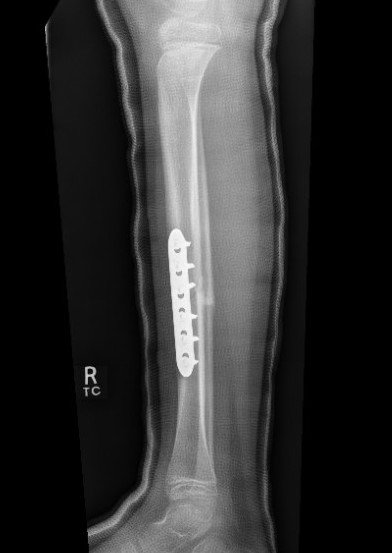

Fixation

- Grade I - reduced +/- percutaneous pinning, long leg cast once wound closed

- Grade II & III - external fixation